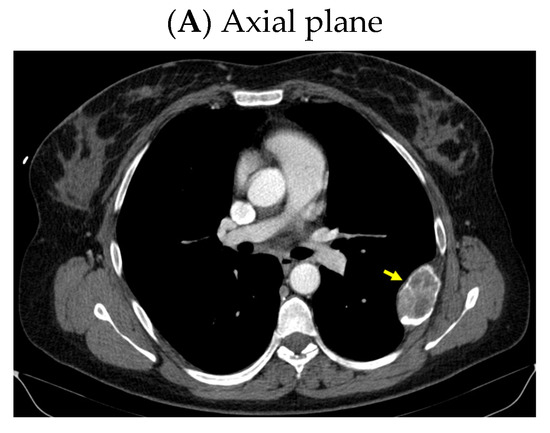

A pelvis CT scan confirmed the osteolytic lesions of the ischium and of the left coxal bone adjacent to the acetabular fossa, measuring 1.97 by 3.29 cm and 1.14 by 1.71 cm, respectively (brown tumors) (Figure 6).

Figure 6.

Pelvis CT scans showing other brown tumors: (A) osteolytic lesion of the left coxal bone adjacent to the acetabular fossa of 1.14 by 1.71 cm (axial plane); (B) osteolytic lesion of the left ischium of 1.97 by 3.29 cm (axial plane).